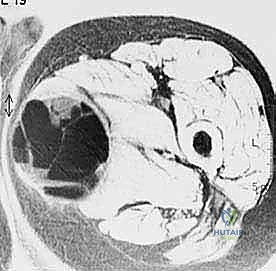

- الأشعة المقطعية (CT Scan): ضرورية لتقييم القشرة العظمية والتكلسات داخل الورم، وللبحث عن أي انتشار في الرئتين.

تختلف الأورام في سلوكها البيولوجي بشكل جذري. الأورام الحميدة، رغم أنها قد تسبب ألماً أو تضغط على الأعصاب المجاورة، إلا أنها لا تنتشر إلى أعضاء أخرى. أما الأورام الخبيثة (مثل الساركوما العظمية Osteosarcoma، ساركوما إيوينغ Ewing's Sarcoma، أو الساركوما الغضروفية Chondrosarcoma)، فلها قدرة تدميرية موضعية عالية وقابلية للانتشار (الانبثاث) إلى الرئتين أو عظام أخرى.